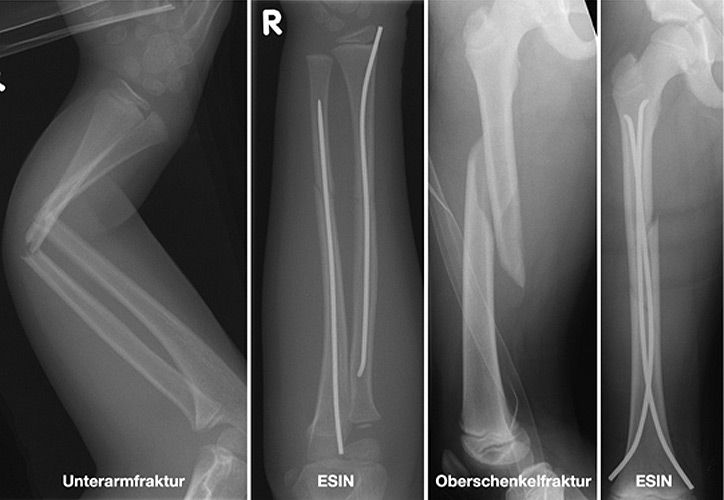

Einige Frakturen müssen auf Grund ihrer Achsabweichung operiert werden. In einer Narkose wird die Fraktur eingerichtet und ggf. mit Metall stabilisiert. Dazu stehen eine Reihe von Methoden (Osteosynthesen) zur Verfügung, die speziell für Kinder entwickelt wurden, um Wachstumsfugen zu schonen und nicht zu verletzen: Die ESIN (elastisch stabile intramedulläre Nagelung) hat sich als minimal invasives Standardverfahren zur Stabilisierung von Schaftfrakturen der großen Röhrenknochen (Unterarm, Oberarm, Unterschenkel, Oberschenkel) etabliert. Die Implantate können über winzige Schnitte eingebracht werden, eine gipsfreie Nachbehandlung ist ein weiterer entscheidender Vorteil.

Andere Verfahren der operativen Frakturversorgung im Kindesalter sind die Kirschner-Draht-Osteosynthese, die Verschraubung, der Fixateur und die Plattenosteosynthese. Metallentfernungen werden ambulant durchgeführt, Nachuntersuchungen zum Ausschluss etwaiger Wachstumsstörungen erfolgen in unserer Frakturensprechstunde.